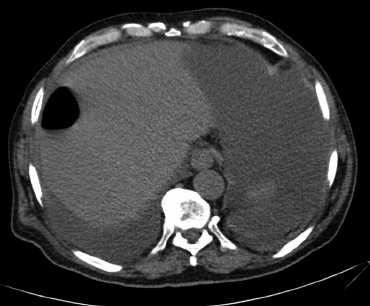

Imágenes y Cirugía

Camila Valenzuela Labra, Raúl Valenzuela Labra, Jaime Cruz Fuentes, Matías Orellana Pérez, Marcelo Villarroel Soto, Hernán Valenzuela Valenzuela